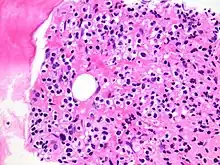

Immune Infiltration

This occurs when immune cells like lymphocytes and macrophages migrate into tissues in response to infection, injury, or inflammation, aiding in defense and healing but potentially contributing to autoimmune diseases if misdirected.[1] Immune cells (especially lymphocytes) also infiltrate into malignant tumors and other neoplasms.[2]